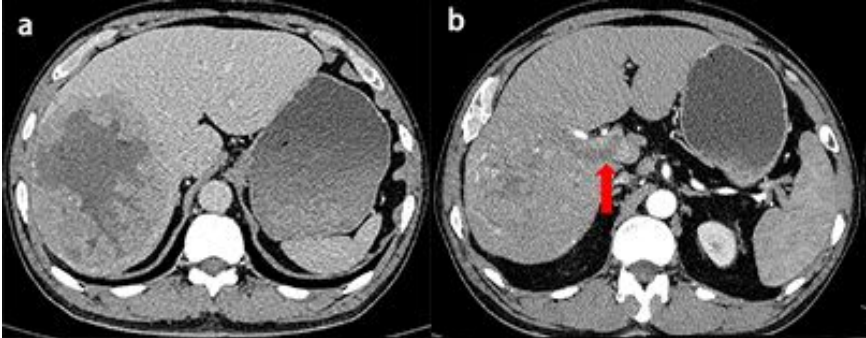

上腹部增强CT示:肝右叶可见低密度肿块,最大横切面135mm×104mm(图a);动脉期肿块增强不均匀,门静脉主干及右支低密度充盈缺损(图b)。